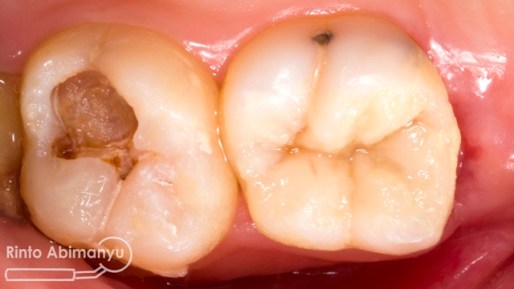

Setelah saya liat keadaan klinisnya ini yang saya lihat…

Gigi 46 terlihat kavitas masih ada karies yang sangat luas dan ada spot sudah terjadi tembus ke kamar pulpa.